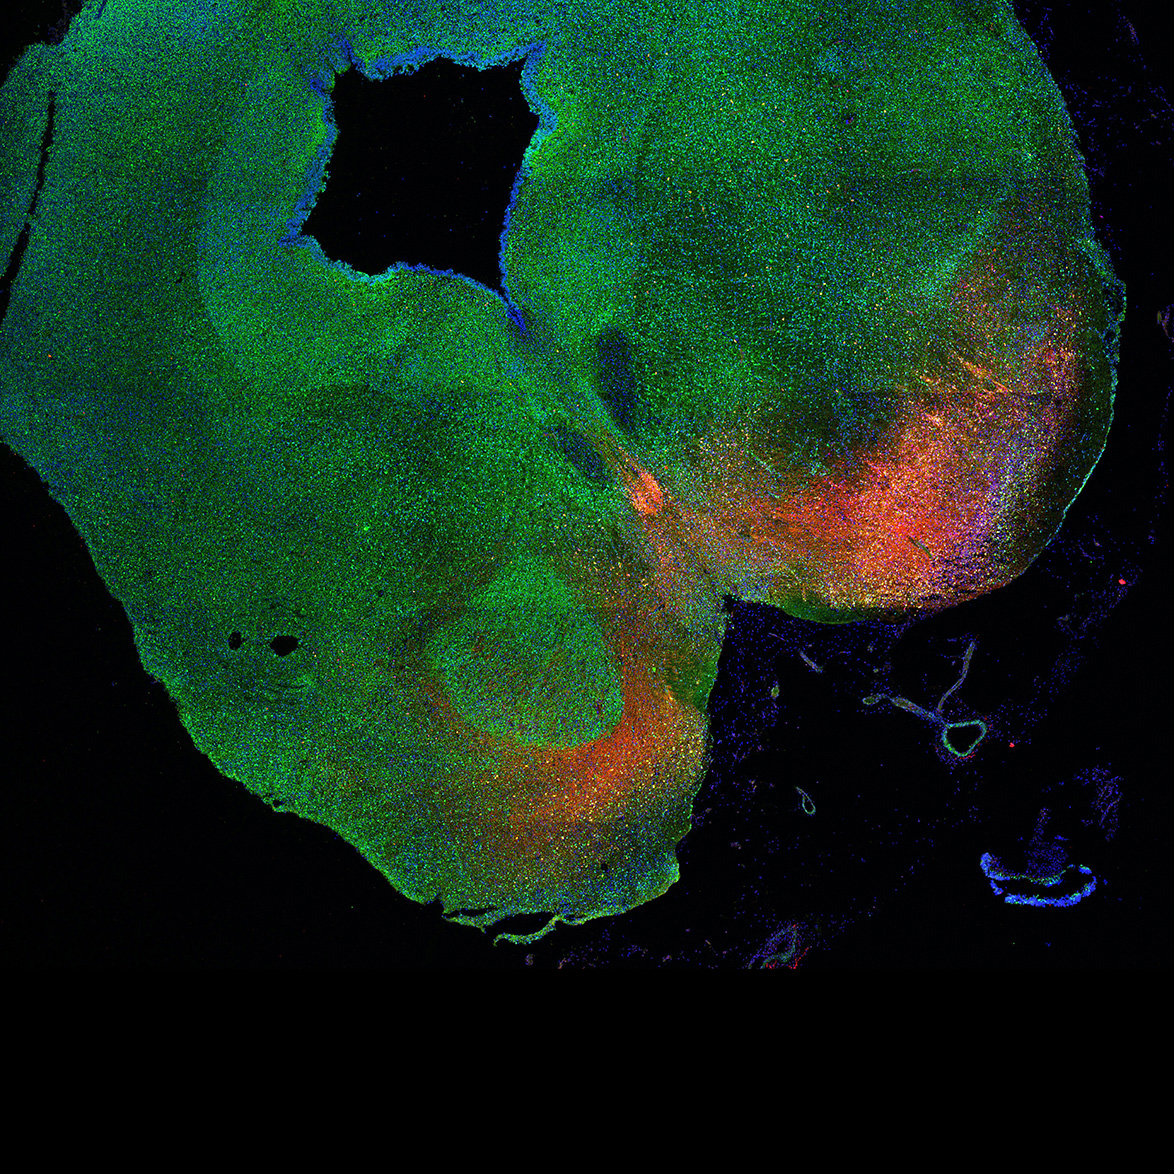

An anatomical analysis of the developing human midbrain from 6 post-conceptional weeks (PCW) to 22 PCW reveals increased tissue complexity, characterized by the emergence of dopaminergic nuclei, as highlighted by immunofluorescence analysis for tyrosine hydroxylase (TH).

Merged

6PCW human midbrain